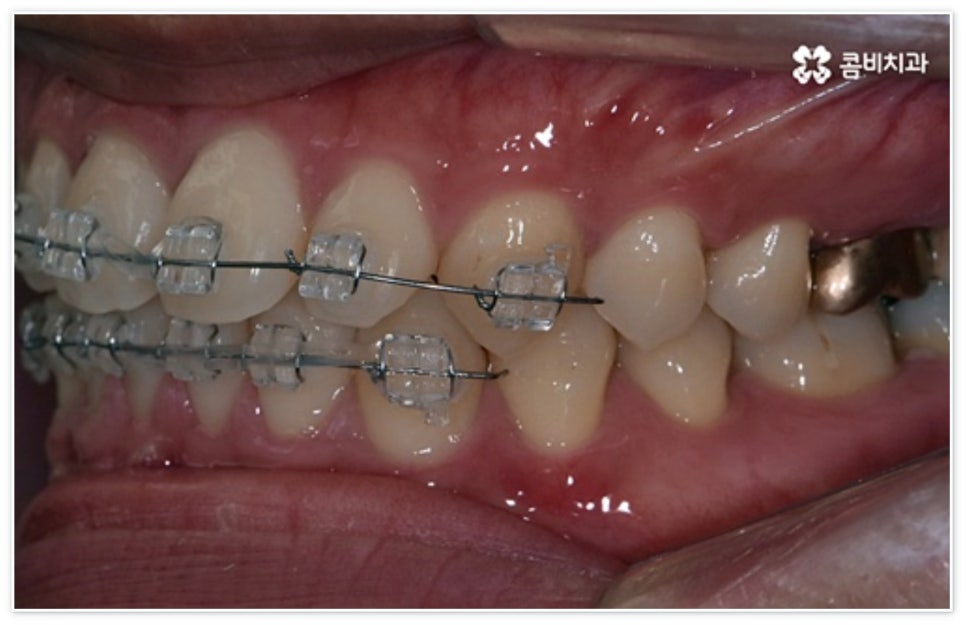

환자분들에 따라 다르지만 통상적으로 전체 교정이 1년에서 2년 반 정도 소요된다면 부분 교정은 6~8개월 정도로 기간 단축이 가능하여 치료에 대한 부담을 줄일 수 있으며 대부분 발치 과정 없이 필요한 부위에만 브라켓을 부착하는 만큼 불편함이 적고 구강 관리도 용이한 편이니 (사진에서 살펴볼 수 있는 케이스) 이에 대해서 자세히 알아보시면 좋을 거예요. 물론 누구나 가능한 것은 아니고 개인의 구강 상태에 따라 진행을 해야 하므로 꼼꼼한 검진과 충분한 상담부터 받아보시길 권유드리고 있습니다.